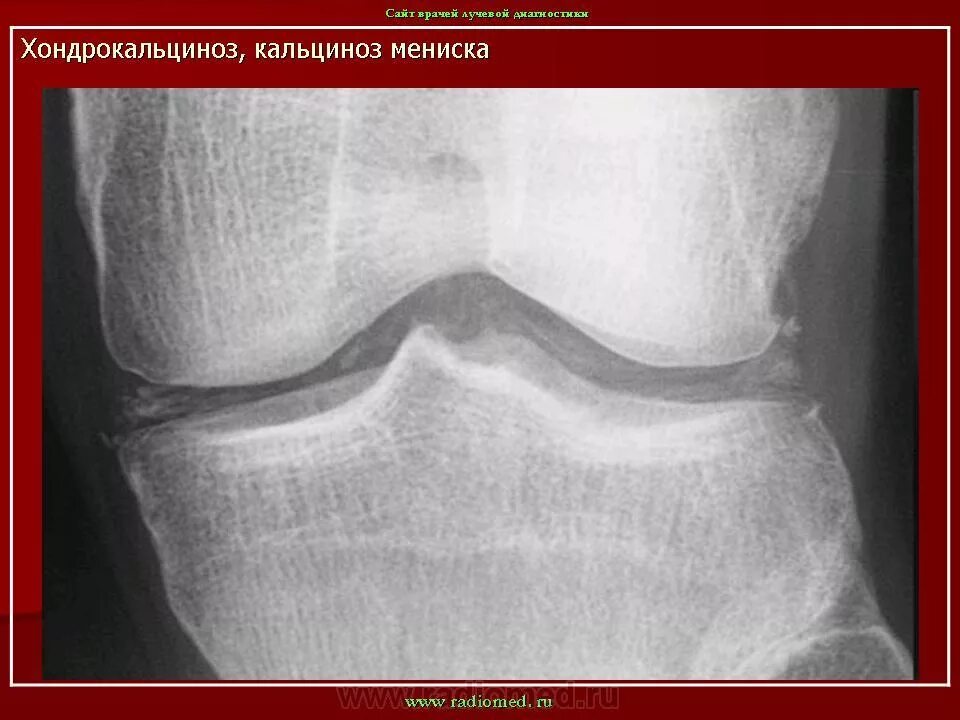

Обызвествление в проекции